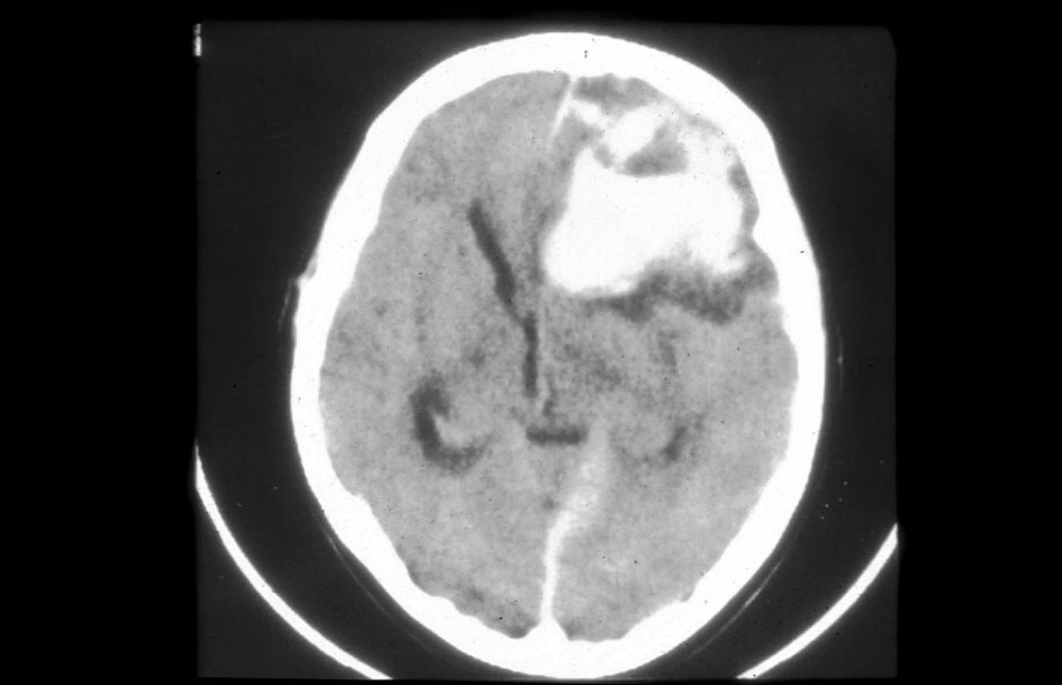

what is shown here?

Intracranial Haemorrhage in Haemophilia

Used to be the commonest cause of death in severe haemophilia

Dense area of bleeding

Midline shifted – not a good outcome